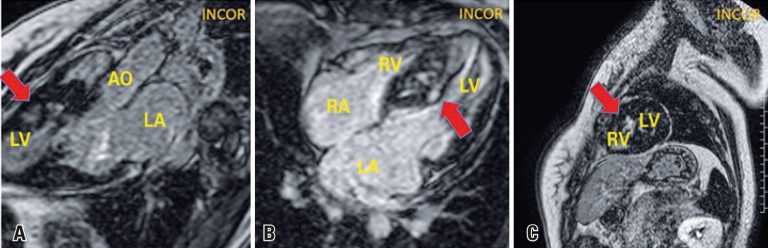

An 18-year-old female patient with hypertrophic cardiomyopathy previously asymptomatic, diagnosed in family screening, who presented progressive dyspnea even upon mild exertion two months before. She was submitted to cardiac magnetic resonance ( and ), which showed asymmetrical myocardial hypertrophy with mid-ventricular septal predominance. The most common form of obstruction of the left ventricle outflow tract in hypertrophic cardiomyopathy is subaortic obstruction,() which generally results from left ventricle outflow tract narrowing by septal hypertrophy and systolic anterior motion of the mitral valve anterior cuspid.()